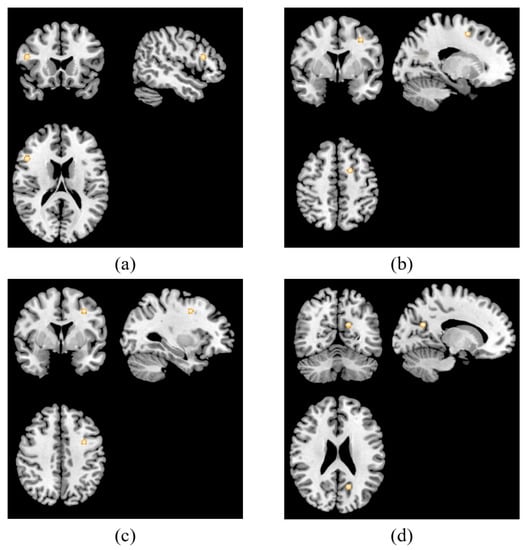

| Region | Cluster Size (mm3) | MNI Coordinates | ALE | p Value | Z Score | BA | ||

|---|---|---|---|---|---|---|---|---|

| x | y | z | max. | |||||

| Main analysis | ||||||||

| Right precentral gyrus | 352 | 60 | 0 | 20 | 0.0078 | 0.0000201 | 4.106458 | 6 |

| Right posterior cingulate | 288 | 21 | 57 | 12 | 0.0075 | 0.0000379 | 3.957385 | 30 |

| Left inferior frontal gyrus | 288 | −46 | 12 | 22 | 0.0073 | 0.0000710 | 3.804717 | 9 |

| Left middle frontal gyrus | 288 | −16 | −18 | 62 | 0.0073 | 0.0000710 | 3.804717 | 6 |

| Resting-state studies | ||||||||

| Right precentral gyrus | 480 | 60 | 0 | 21 | 0.0078 | 0.0000137 | 4.194821 | 6 |

| Right posterior cingulate | 448 | 21 | 57 | 12 | 0.0075 | 0.0000299 | 4.013568 | 30 |

| Left inferior frontal gyrus | 448 | −46 | 12 | 22 | 0.0073 | 0.0000611 | 3.842041 | 9 |

| Left superior frontal gyrus | 448 | −15 | −18 | 63 | 0.0073 | 0.0000610 | 3.842041 | 6 |

| Task-related studies | ||||||||

| Right middle frontal gyrus | 384 | 48 | 20 | 18 | 0.0063 | 0.0000038 | 4.476675 | 46 |

| Left sub-gyrus | 360 | −18 | 4 | 52 | 0.0062 | 0.0000156 | 4.165172 | 6 |

| Left middle frontal gyrus | 352 | −32 | 2 | 42 | 0.0060 | 0.0000238 | 4.066664 | 6 |

| Left posterior cingulate | 344 | −16 | −60 | 24 | 0.0062 | 0.0000156 | 4.165172 | 31 |